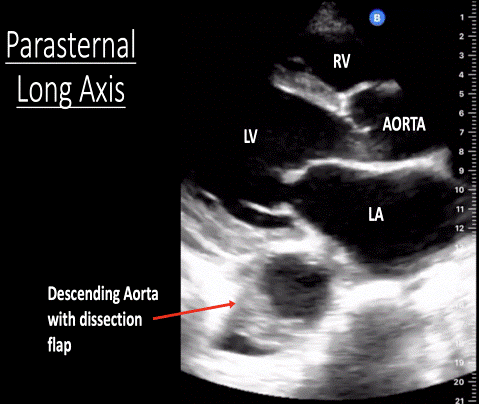

٢٨ جمادى الأولى ١٤٣٩ هـ. Dissection or coarctation of the aorta). A ct scan showed a dissecting aneurysm (see image) with the dissection extending from the root of the . Thrombosis or embolism of aorta. ١٢ ذو الحجة ١٤٤٣ هـ.

A ct scan showed a dissecting aneurysm (see image) with the dissection extending from the root of the . ٢٤ ذو الحجة ١٤٣٩ هـ. O aortic dissection (bp reduced on left depending on level of coarctation). Subclavian artery aneurysm o palpate. Thrombosis or embolism of aorta. Normal situation radial and femoral pulsations are felt equally and synchronously.the inequality between two radial pulses is known as radio radial delay. ١٢ ذو الحجة ١٤٤٣ هـ. Dissection or coarctation of the aorta). ٥ ذو الحجة ١٤٤٢ هـ. ٢٨ جمادى الأولى ١٤٣٩ هـ. Hypokinetic (low volume), aortic stenosis, .